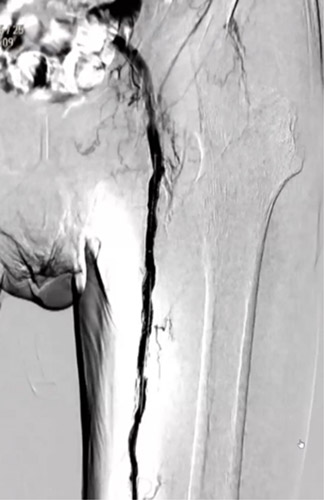

DAは閉塞していたが内腔はあるので穿刺を検討したが、難しいと判断しPTAを穿刺した。PTA経由でATAにレトログレードアプローチを行いDAからシースを挿入するため、1gワイヤーを進めたがATA(Anterior Tibial Artery)方向へワイヤリング出来ないため、Zizai™をPOP方向へ進め造影した(図3)。ATA入口部は狭窄しており、更に末梢は閉塞していることを確認した。ATA入口部へワイヤー通過に成功し急峻な角度ではあったがZizai™を追従させ(図4)、ATAは閉塞血管でありワイヤールートはSubでも良いと判断しワイヤーナックルにて末梢まで進めた。DAを18G針で穿刺をしワイヤーランデブーに成功した(図5)。その後、DAに4Frシースを挿入し、2.5㎜径バルーンでATAを拡張したあと、PTAのワイヤーとZizai™を抜去後にアプローチサイトの止血を行い、ATAの4Frシースからガイディングシースへ入れ替えを行った。